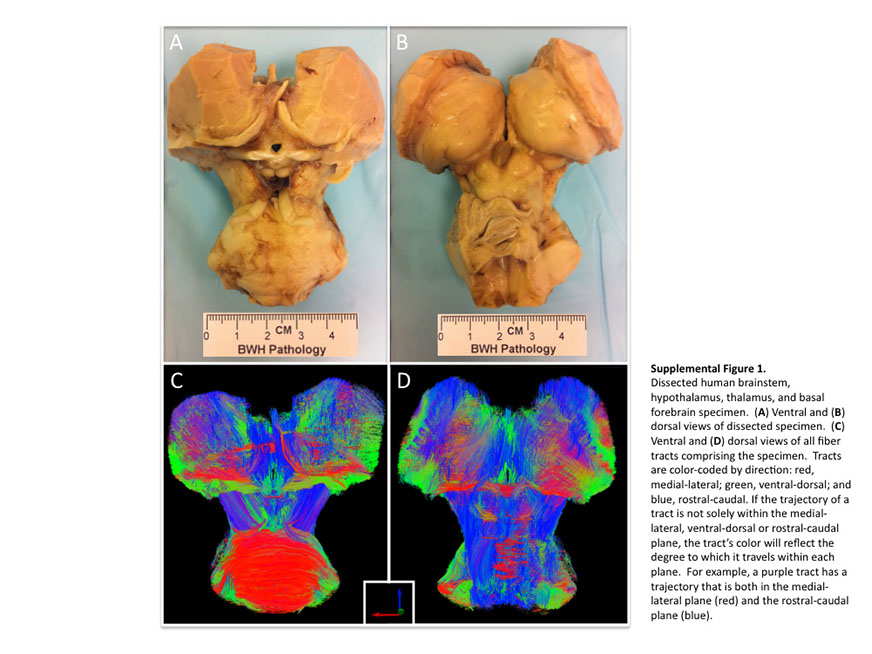

Many observations suggest that CFS could derive from residual damage to the reticular activating system (RAS) of the upper brain stem and/or to its cortical projections. It should be pointed out that although the larger right greater than left asymmetry in regional cerebral blood flow is found at the parietotempotal level in CFS patients as compared to healthy controls, no significant correlations are found between frontal tracer uptake and right-left parietotemporal asymmetry, on the one hand, and clinically relevant CFS dimensions on the other. Damage to the RAS could be produced by a previous viral infection, leaving functional defects unaccompanied by any gross histological changes.

In this respect, fluorine-deoxyglucose positron emission tomography showed specific metabolism abnormalities in CFS patients (hypometabolism in right mediofrontal cortex and brainstem) as compared with both healthy controls and depressed patients. The most relevant abnormality is brain stem hypometabolism, which has been also reported in single-photon emission computed tomography studies and seems to be a marker for the in vivo diagnosis of CFS